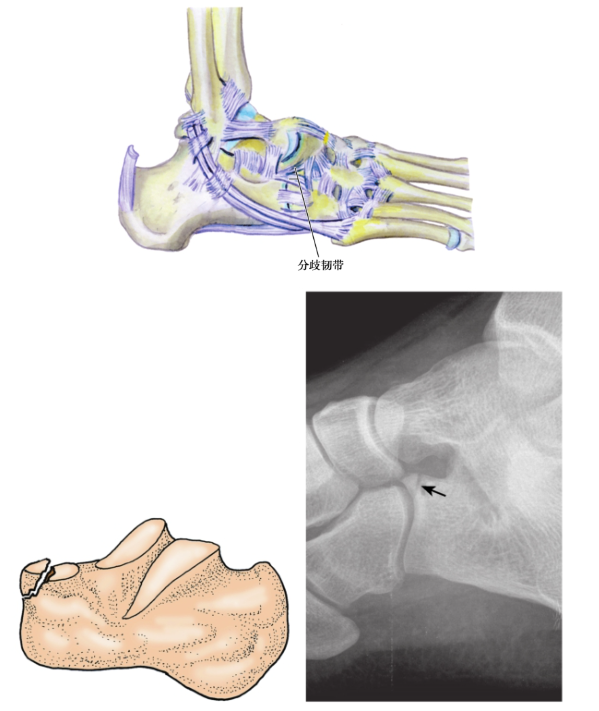

1、跟骨前突骨折:

两种不同损伤机制引起跟骨前突骨折。

(1) 跟骨前突撕脱骨折:

多见,常由足跖屈、内翻应力引起。暴力引起附着在跟骨前突及足舟骨、骰骨近端的分歧韧带紧张,造成跟骨前突撕脱骨折。骨折线伸入跟骰关节,骨折块较小,典型的情况下包含极少量的关节面(图5)。

图5 跟骨前突撕脱骨折

较少见,足强力外展挤压跟骰关节面造成。跟骨前突的压缩骨折块特别大,波及跟骰关节,常常出现骨折移位。临床表现为跟骨前突部位的触痛,容易被误诊为足踝扭伤(图6)。